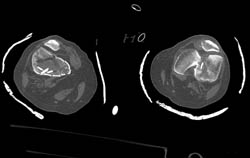

High Resolution Details of Epiphysis